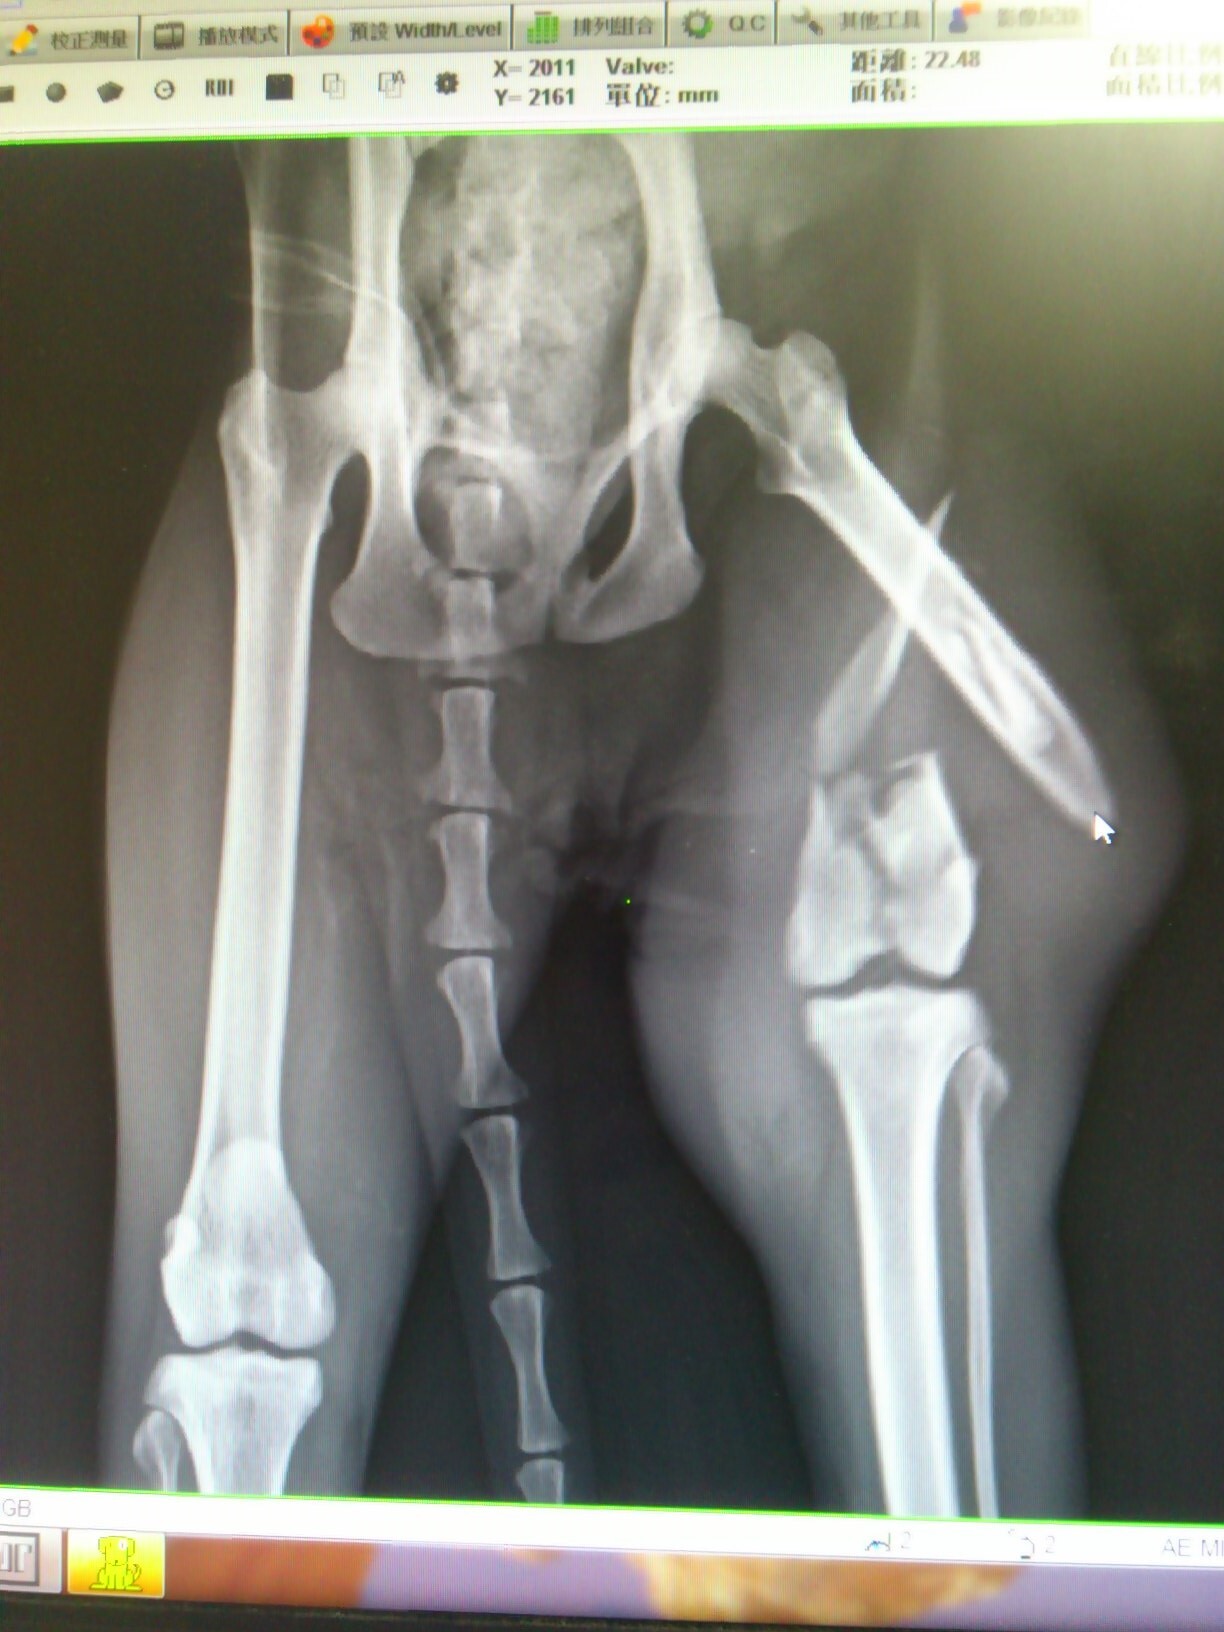

主題: 哺乳母貓車禍造成嚴重骨折 申請者姓名: 金承穎 花色: 申請日期: 2013-06-11 16:59:51 申請者部落格: 申請者臉書網址: 所在縣市/合作醫院: 台北市/其他院所醫助專案(醫院請先MAIL溝通) 治療費用: 61900元 需求人數: 64人 已結案 (2013-09-03 16:23:02) 報名人員: Jong Chia Liu x2(已付款)、吉布弟(已付款)、Katilin Chang(已付款)、momo x2(已付款)、Yin-Chia Su(已付款)、Norman Wu(已付款)、philip x2(已付款)、smilecat x2(已付款)、小節(已付款)、小麥(已付款)、suxiwen x2(已付款)、陳倩婷(已付款)、樂樂(已付款)、connie242(已付款)、Ping Hussard(已付款)、王麗惠(已付款)、莊又臻(已付款)、Wanhua Chan(已付款)、Lulu Lin、Lulu Lin(已付款)、Peggy Tseng(已付款)、韋懷思(已付款)、緣緣寶貝 x2(已付款)、Aretha Lin(已付款)、zofia(已付款)、Candy Wu(已付款)、Stephen(已付款)、Ted x2(已付款)、愛麗絲(已付款)、Ting-Ju Chen(已付款)、Rean Wu(已付款)、Gina Chen-hui Yu x2(已付款)、黃亞凡(已付款)、Sue Su(已付款)、Yuchun Chao(已付款)、joey(已付款)、Wei Lin(已付款)、蘇小優(已付款)、阿惹(已付款)、Meng-Ning Wang(已付款)、古法蘭(已付款)、古法蘭(已付款)、林嘉南(已付款)、游妃妃(已付款)、vivian(已付款)、lavinia x2(已付款)、Takeshi Kan(已付款)、kayu x2(已付款)、煎塔媽(已付款)、蔡秀芳(已付款)、家有三色喵(已付款)、Vivienne Peng(已付款)、Chen Ping、Chen Ping、Bess(已付款)、小p(已付款)、Ou Han(已付款)、 候補人員: 動物病情說明: 4/12早上10點左右.在承德路.百齡橋下發現牠.應該是被車撞..不然不會那麼嚴重.送醫發現.牠的左後肢嚴重開放性骨折,斷成數截、肝指數破表.為了保住他的腳,懇求協會幫忙協助幫忙安排就醫,虎虎到院時就有嚴重脹奶的問題,回到發現虎虎的地方,完全不見小貓蹤影,只能請醫師多注意虎虎的狀況

4/14日虎虎還是不願意進食,車禍對他的創傷甚巨,醫師緊急安置食道餵管,方便灌食補充營養,4/22日才進行大腿粉碎性骨折修復手術,數日後,虎虎的乳房脹奶發炎化膿,又進行手術清創,目前已經先出院照顧安置,虎虎的腳還需要做外包紮固定,等待他慢慢復原。